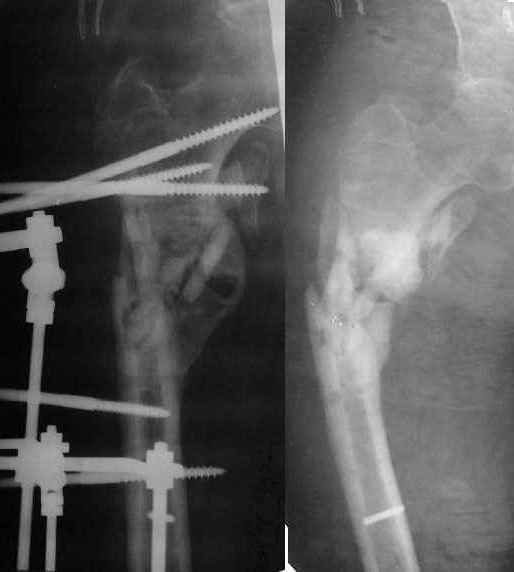

Re: Ложный сустав в/3 плечевой кости!

Неудачный остеосинтез пластиной: поломка винтов. После удаления сформирался гиполастический ложный сустав. Остеосинтез АВФ, циклическая компрессия-дистракция в области ложного сустава привела к формированию хорошей рентгенологической костной мозоли. Через 1,5 месяца ходил в аппарате без дополнительных средств опоры. Через 6 месяцев после клинической пробы - демотаж. Через 4 месяца после демонтажа - лизис костной мозоли, рецидив деформации.